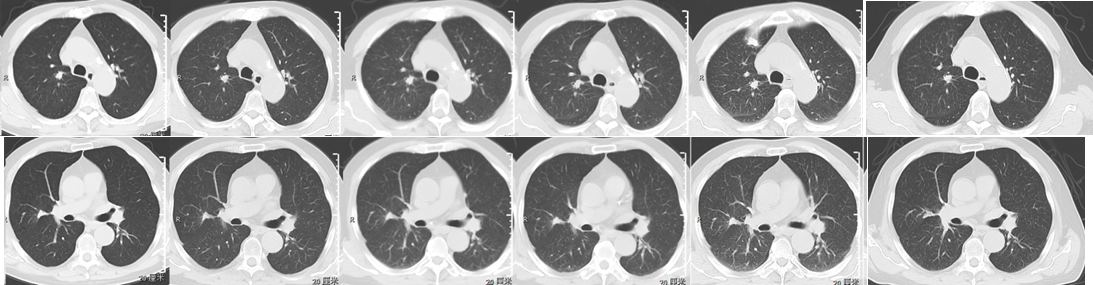

维持治疗3周期后A  6周期后B  9周期后C  12周期后D  15周期后E  18周期后F

3.jpg

A             B              C              D                E               F